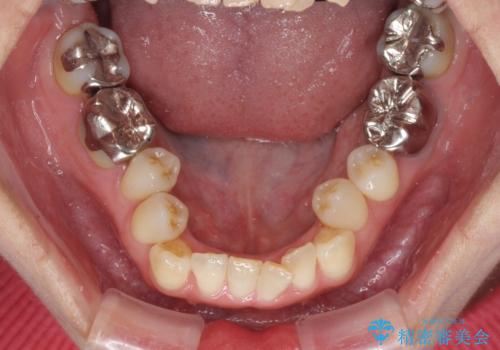

- 前歯の反対咬合を気にして来院された患者様です。

上顎骨の幅が下顎骨よりも小さいので、拡大装置により骨幅を広げて上下関係を改善すると同時にワイヤー矯正で反対咬合の改善を図り、その後インビザラインにて歯並びを整えることとしました。

急速拡大装置の使用により奥歯の咬み合わせが劇的に変わり、その変化を利用して反対咬合を改善することができました。

治療期間中は奥歯が咬み合わず、食事が取りにくいなどの不都合がありましたが、最終的にはきれいに整えることができました。